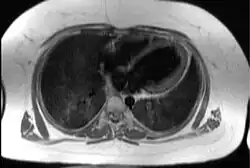

Transaxial image of the chest at the level of the heart illustrating the typical degree of subcutaneous and epicardial adipose tissue (shown in white) in a patient with Alström syndrome; hence the difficulty in imaging by echocardiography